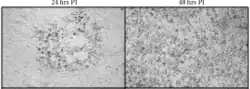

B virus spread in murine cells with time at 24 and 48-hours post infection (PI)